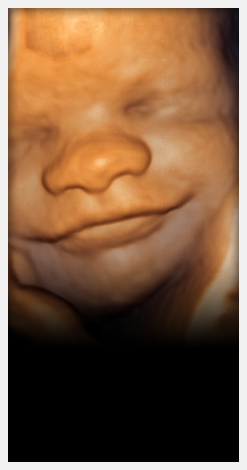

Bem-estar

da paciente e da família

Todos os exames são realizados em aparelhos de alta tecnologia e acompanhados pela Dra. Ana Lúcia Isotton, com 25 anos de experiência.